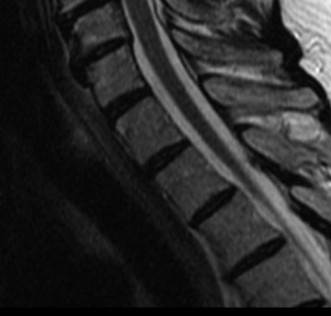

Magnetic Resonance Imaging and the Posterior Ligamentous Complex

To definitively assess the integrity of the soft tissue stabilizers and the neural elements, a Magnetic Resonance Imaging (MRI) scan without contrast was performed. Historically, textbooks propagated the "50-50-25 rule," suggesting that a burst fracture was inherently unstable if it exhibited >50% canal compromise, >50% loss of vertebral body height, or >25 degrees of kyphosis. Modern spine trauma surgery has largely debunked this rigid radiographic dogma. We now understand that these bony metrics alone do not dictate mechanical instability. The true arbiter of stability is the Posterior Ligamentous Complex (PLC).

The MRI, particularly the Short Tau Inversion Recovery (STIR) and T2-weighted sagittal sequences, provided the definitive diagnosis. The images demonstrated profound hyperintensity and discontinuity of the ligamentum flavum, the interspinous ligaments, and the supraspinous ligaments at the T12-L1 level. The facet joint capsules were also disrupted, indicated by fluid within the joints. This complete failure of the PLC means the posterior tension band is gone. Regardless of the bony parameters, this spine cannot resist physiological flexion loads. If treated non-operatively, this injury will inevitably lead to progressive kyphosis, delayed neurological deficit, and intractable pain.